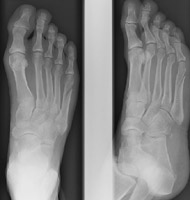

- Click on the image for a larger versionCAP and oblique radiographs of the foot. In contradistinction, this patient sustained a fracture of the proximal aspect of the fifth metatarsal. Greenspan terms this an avulsion injury.